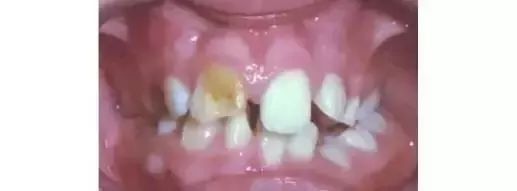

然而並沒有好好地護理,不過冇好好護理,剛開始是這樣的。

隔離嗰個大婆講,母乳牙要換嗰,無需要補嘅。然後就變咗成咁樣。

家長開始擔心,不過村口擺地攤“100種塊牙”嘅老大哥又講咗,“呢係咩事呀?換牙啦就算啦!”於是,牙齒就變成噉樣啦。